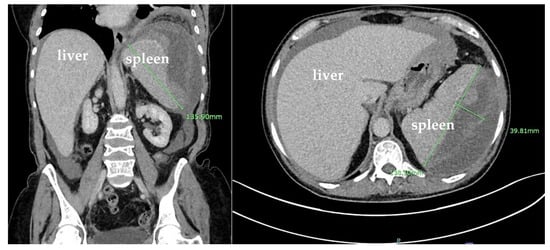

The CT angiography (CTA) of the abdomen and pelvis was negative for active bleeding. The patient was discharged 9 days after the stabilization of anemia and the resolution of her nausea and vomiting. However, she returned to the hospital 15 days later due to a syncopal episode and persistence of her abdominal pain. During that admission, she was hypotensive and was found to have anemia with hemoglobin of 6.9 g/dL that required another transfusion of one unit of packed RBCs. Repeated CT of the abdomen and pelvis showed large mixed-density splenic subcapsular hematoma of unclear etiology, which had significantly increased in size since the prior study, this time measuring 13.6 × 13.8 × 4 cm (previously 12 × 11 × 0.1 cm), with a mass effect on the splenic parenchyma and an increase in the moderate-volume hemoperitoneum (Figure 4).

Figure 4. Coronal and sagittal plane computed tomography (CT) scans with IV contrast of the abdomen and pelvis showing large mixed-density splenic subcapsular hematoma of unclear etiology, which significantly increased in size since the prior study, this time measuring 13.8 × 13.6 × 4 cm (previously 13.2 cm in greatest dimension), with a mass effect on the splenic parenchyma and an increase in the moderate-volume hemoperitoneum.